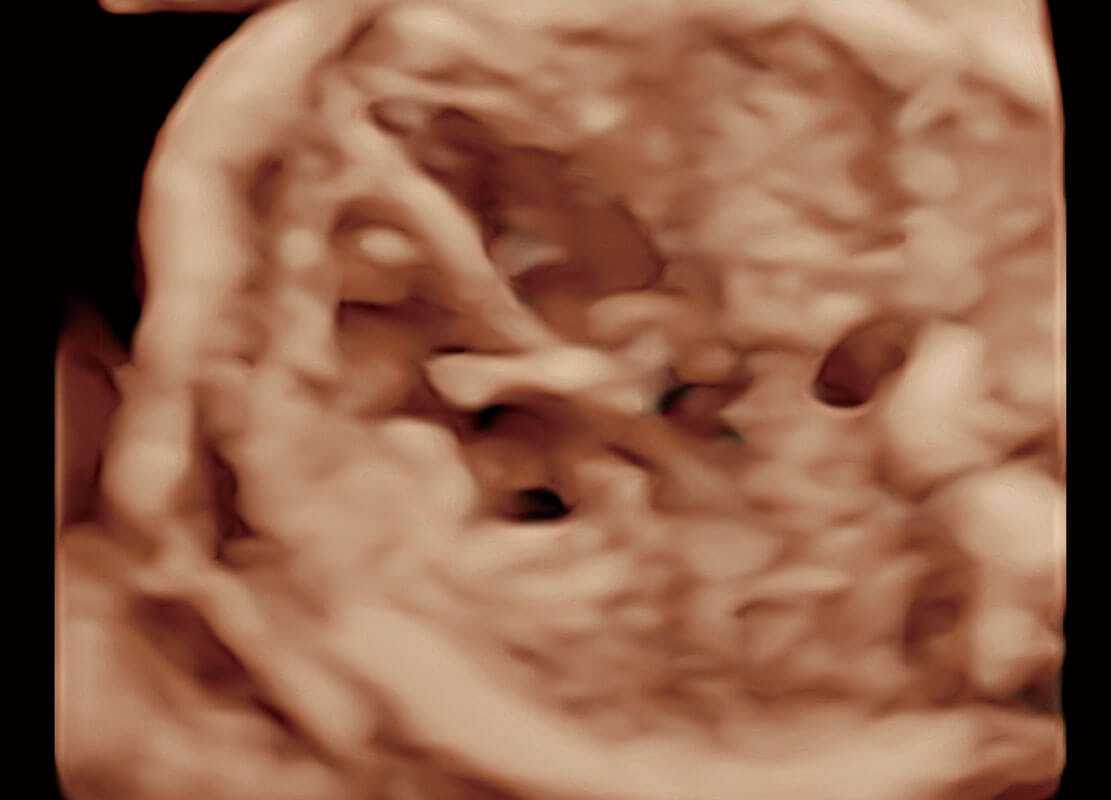

高分辨率容積成像-早孕胎兒

P60在胎兒早孕期超聲篩查中為您帶來優(yōu)異的圖像質(zhì)量。